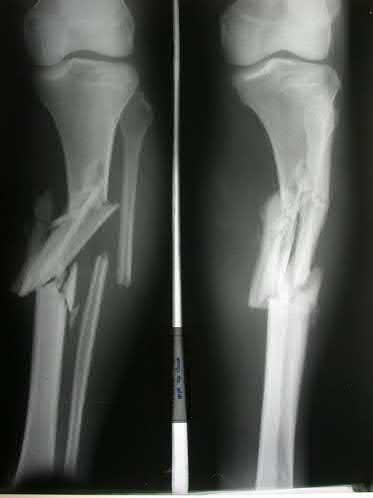

A 25-year-old female is involved in a motor vehicle collision. She presents with the isolated injury seen in Figures A through D. Her leg is swollen but her skin is intact. She has no clinical signs of compartment syndrome. Which of the following treatment options will allow for maintenance of fracture alignment and minimize the risk of soft tissue complications?

The patient presents with a closed distal third metaphyseal-diaphyseal distal tibia fracture with simple intra-articular extension. Immediate intramedullary nailing along with percutaneous fixation of the articular component provides appropriate restoration of length, rotation and alignment and minimizes the risk of wound complication.

Displaced distal third tibia fractures may be associated with simple intraarticular extension. Operative treatment of intra-articular distal tibia fractures has historically been performed with open reduction and internal fixation. Early open reduction and plate fixation of pilon fractures has been associated with high rates of infection and wound complication. In select patterns with simple articular extension, percutaneous screw fixation and medullary nailing may provide appropriate reduction with minimal soft-tissue risk.

Marcus et al. evaluated the outcomes of immediate intramedullary nailing and percutaneous fixation of simple intra-articular distal tibia fractures (AO/OTA 43 C1 and C2). The authors found excellent rates of union and alignment, however caution against broad application of this technique until more rigorous randomized studies can be performed.

Sirkin et al. retrospectively evaluated the results of a staged approach to management of intra-articular distal tibia fractures with temporary bridging external fixation followed by open reduction and internal fixation (ORIF). The authors found decreased rates of wound complication and infection compared with prior studies.

Figures A and B demonstrate a distal third tibial shaft fracture with simple intra-articular extension. The axial and coronal CT cuts in Figures C and D further clarify the articular injury. Illustrations A and B demonstrate a comminuted distal third tibial fracture with simple intra-articular extension. Illustrations C and D are fluoroscopic images of the same injury after intramedullary nailing and percutaneous fixation of the articular component.